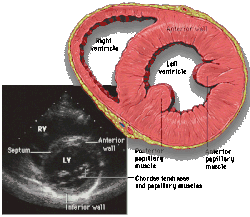

Parasternal short axis (PSAX)

This view is obtained in the same window as the parasternal long, but with the probe rotated 90°. In this view, the aortic valve is seen in cross-section with the right ventricular inflow & outflow tracts visible with the tricuspid valve as well. Pulmonary valve is not visible in this view. Both the right and left atria are visible.

The standard PSAX view is at the level of the aortic valve, but moving the probe along the long-axis can review the LV outflow tract, LV at the base, and LV at the midsection.

Structures visible:

- Aortic valve in short-axis

- Aortic valve dysfunction, aortic sclerosis/stenosis

- Tricuspid valve in long-axis

- Pulmonary valve in long-axis

- Right ventricle, including inflow and outflow tracts

- Left ventricle in short-axis

- Closer to the base can reveal the left ventricular outflow tract

- At the level of the base can show the movement of the mitral valve leaflets in short-axis

- At the level of mid-LV can show papillary muscles

Measurements in this view can be used to quantify the heart:

- Aortic valve area by planimetry

- Color doppler of all four valves

- Spectral doppler of tricuspid and pulmonary valves